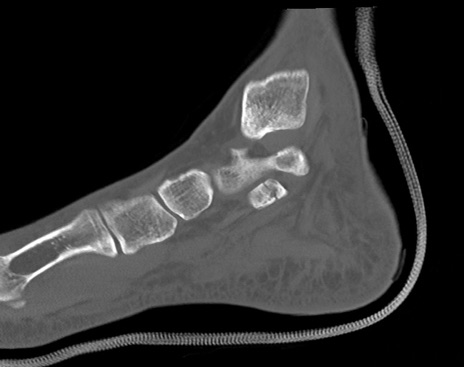

症例37 左足関節CT(矢状断像)

左足関節CT